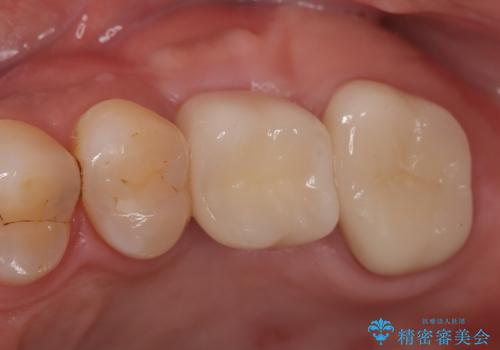

【歯牙破折】インプラントによる咬合回復

歯牙の破折を認めたため抜歯をし、インプラントにて咬合回復をしました。

抜歯後、骨増生を行ったのちインプラントを埋入しています。